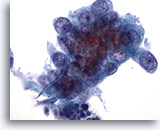

Figure 78

Bronchial wash

At lower magnification a large cell, highly suspicious for squamous cell carcinoma, is present. 20x

Bronchial wash

At lower magnification a large cell, highly suspicious for squamous cell carcinoma, is present. 20x

Figure 78

Bronchial wash

At lower magnification a large cell, highly suspicious for squamous cell carcinoma, is present.

20x

Bronchial wash

At lower magnification a large cell, highly suspicious for squamous cell carcinoma, is present.

20x